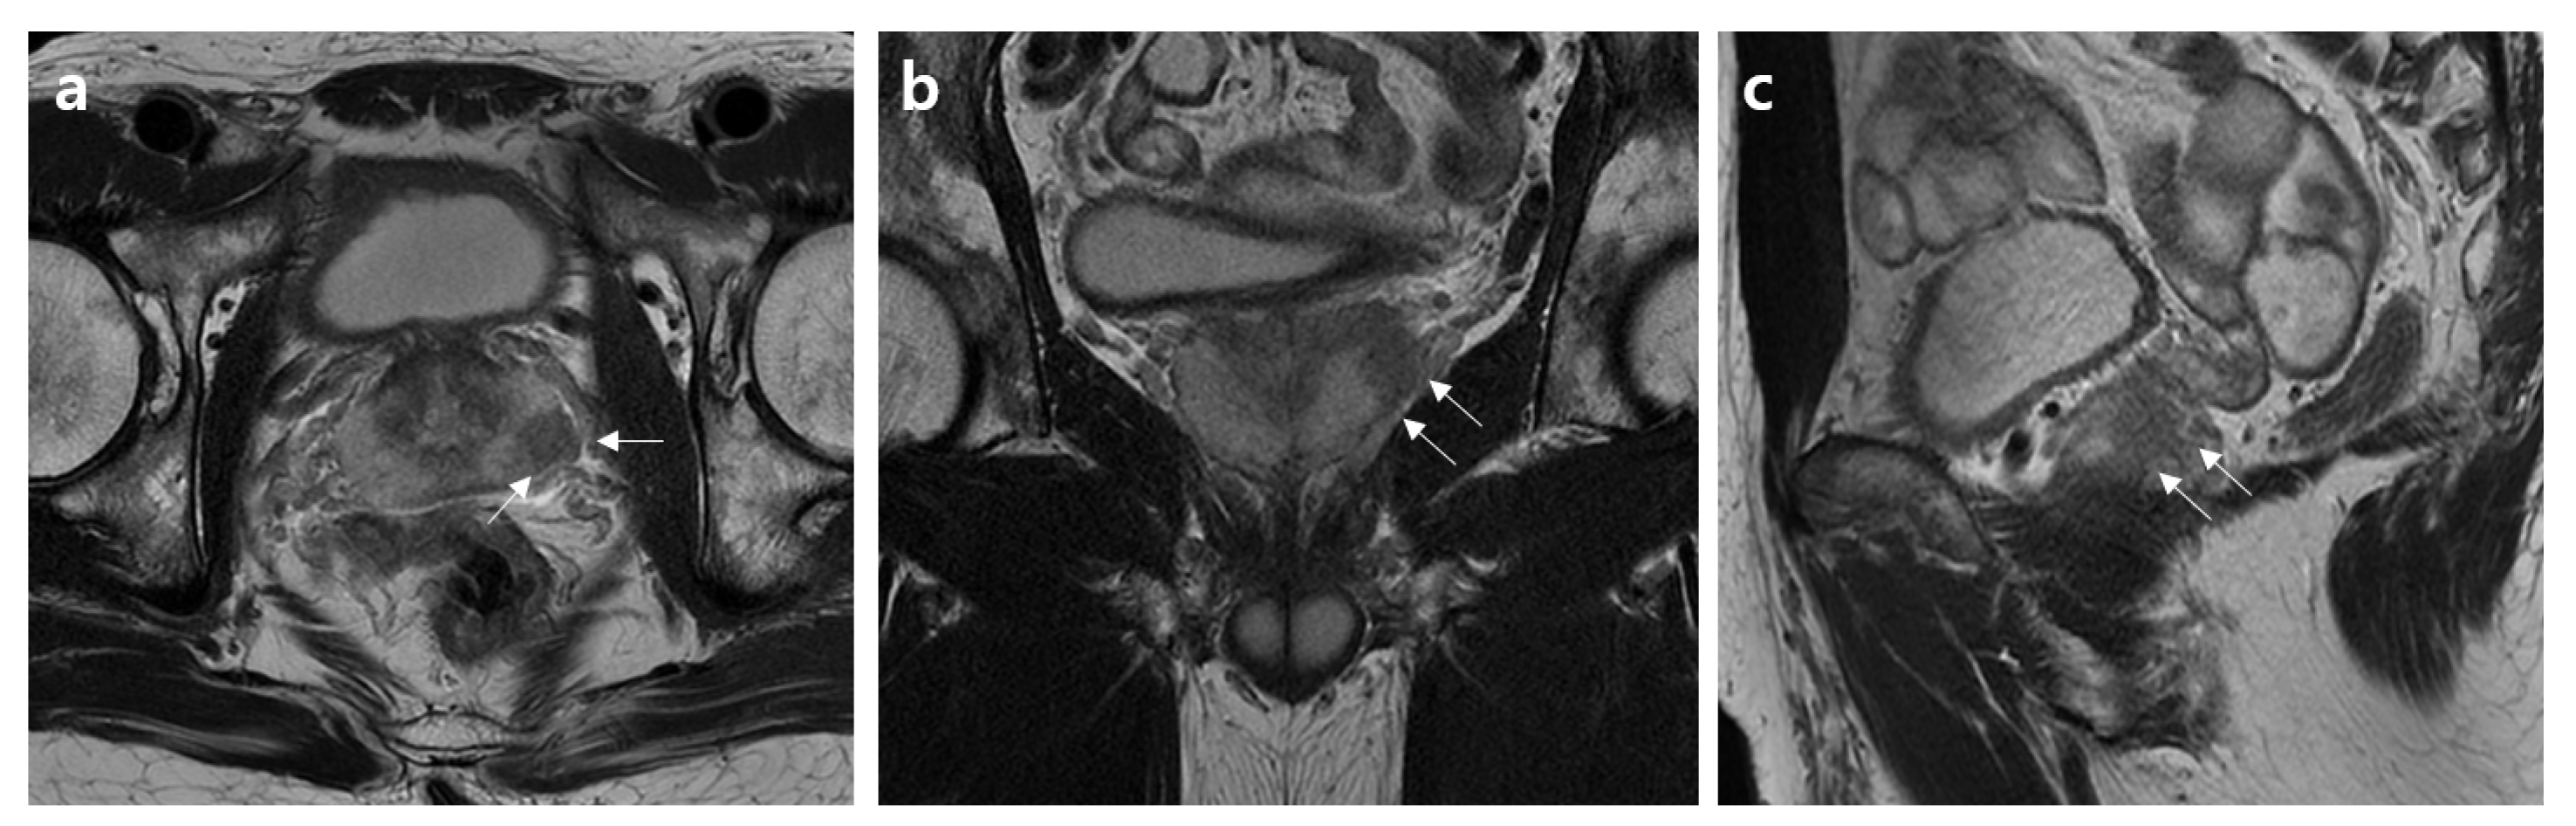

2.2. MRI Assessment